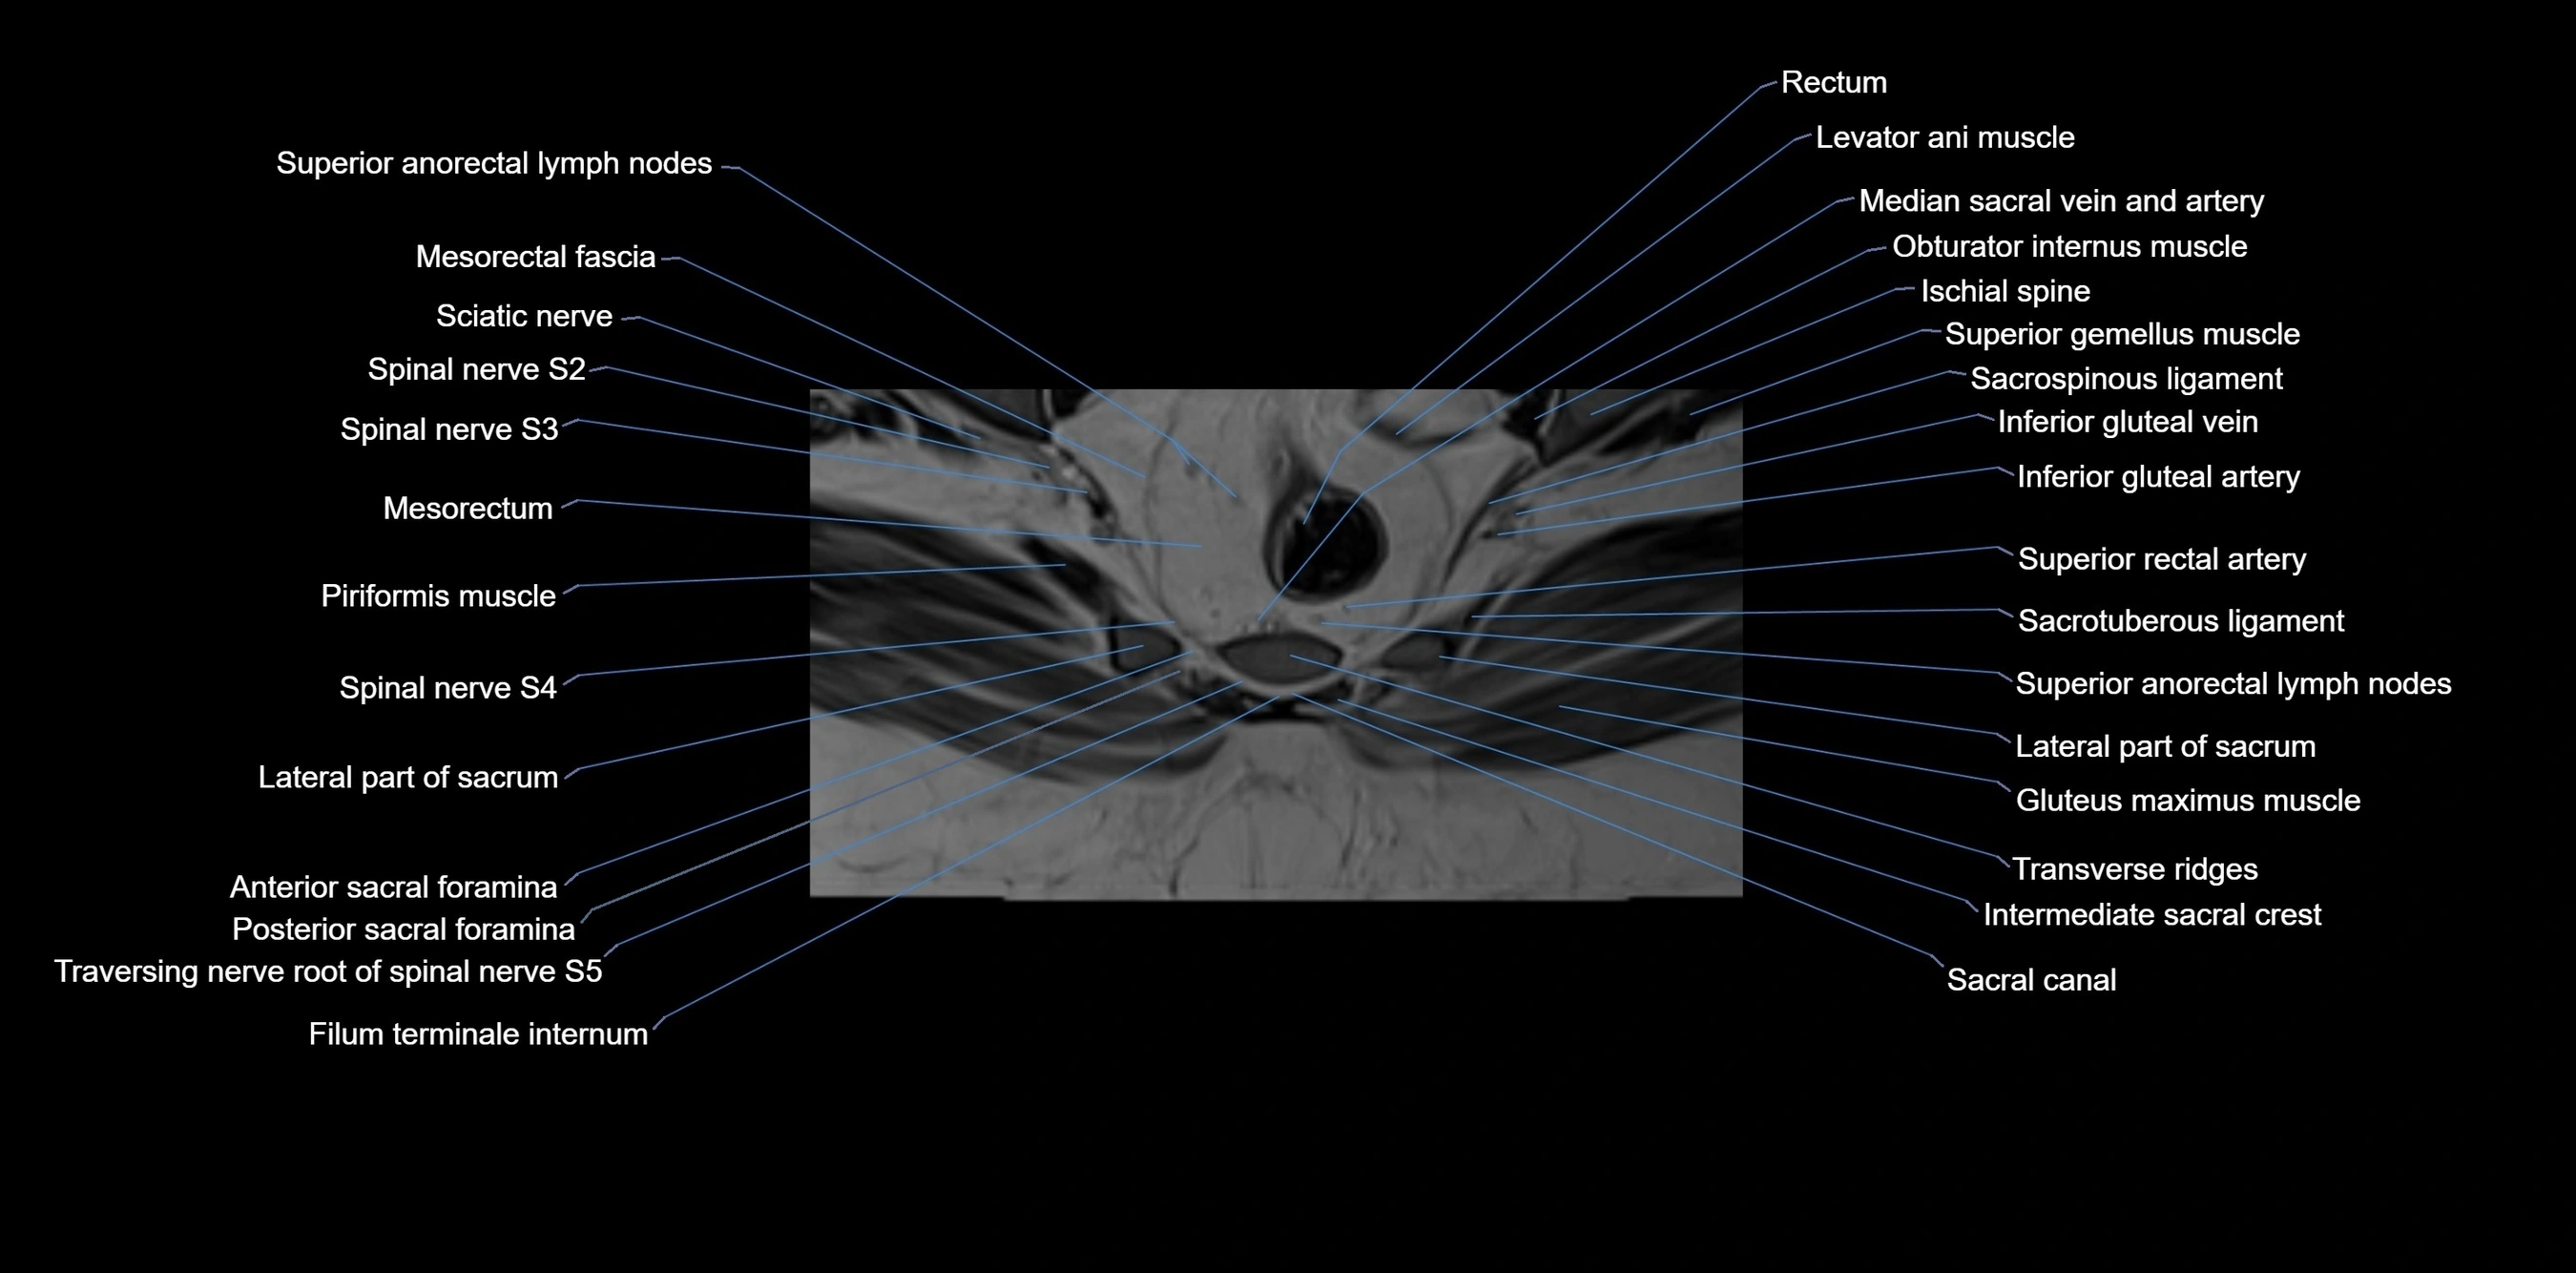

MRI image

image